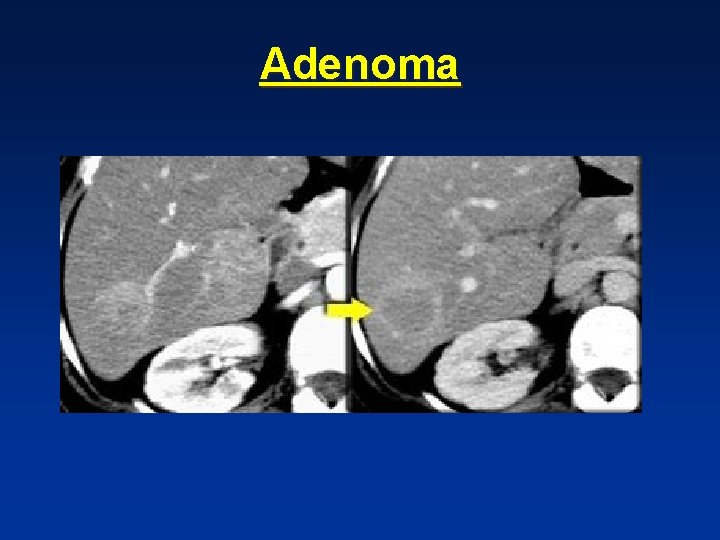

Adenoma

• Best diagnostic clue: spherical well defined hypervascular and heterogenous mass due to fat & hemorrhage. • Symptomatic in 80%-abdominal pain- ( FNH asymptomatic in 80%) • 98% in yoyung females taking oral contraceptives • Not seen in males unless on anabolic steroids or with glycogen storage disease.

• Adenoma showing capsule in delayed phase

Capsule • Hepatocellular carcinoma “ HCC “ • Adenoma • Biliary cystadenoma